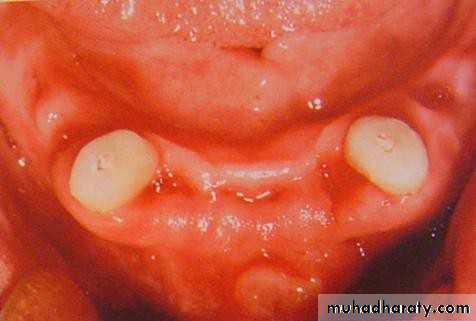

• 3) Medium short (2-4mm):

• a) proximal walls should be parallel for max. frictional fit• b) adjacent abutments better to be splinted

• c) tooth is non vital

• d) used when a favourable C/R ratio

• is needed

• 4) Short (1-2mm):

• a) conform to the curvature of the alveolar ridge (Dum-shape).• b) very low profile.

• c) indicated for max. favourable C/R

• ratio.